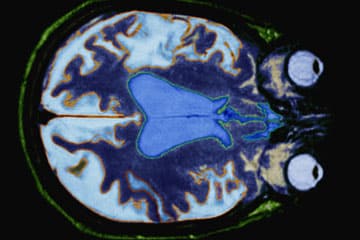

Selon l’Autorité de sûreté nucléaire (ASN), la radioprotection se définit comme « l’ensemble des règles, des procédures et des moyens de prévention et de surveillance visant à empêcher ou à réduire les effets nocifs des rayonnements ionisants produits sur les personnes directement ou indirectement, y compris lors des atteintes portées à l’environnement ». Elle a donc pour objectif de protéger les patients en édictant toute une série de bonnes pratiques, régies par trois principes fondamentaux :

Une trop grande exposition ou une mauvaise utilisation de la radiologie peut avoir divers effets néfastes sur le patient. Ceux-ci peuvent être déterministes, entraînant la mort d’une cellule, ou stochastiques, la cellule pourra se régénérer, mais de manière incomplète.